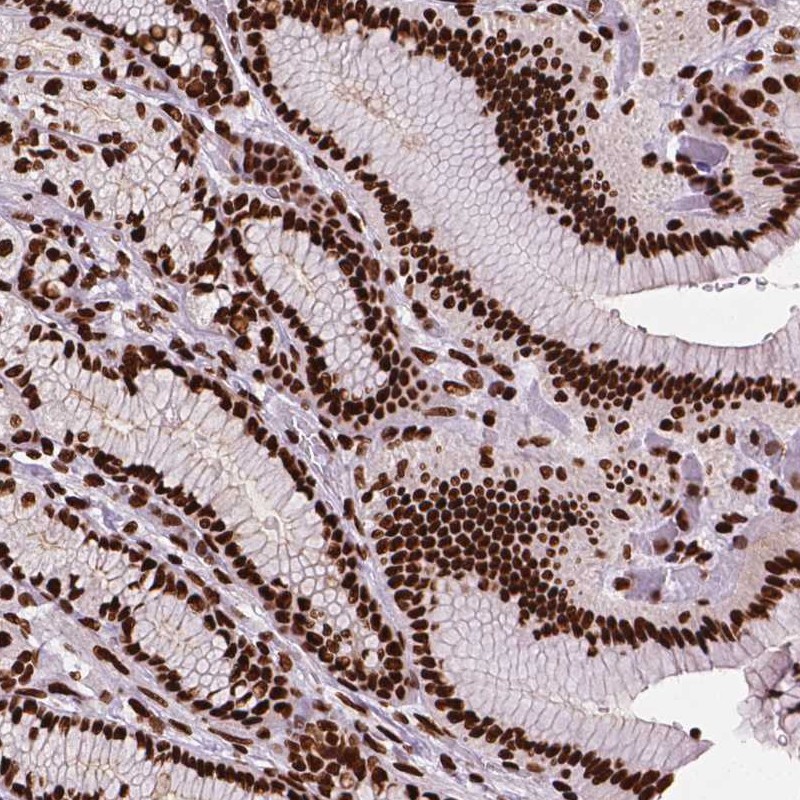

Immunohistochemical staining of human stomach shows strong nuclear positivity in glandular cells.